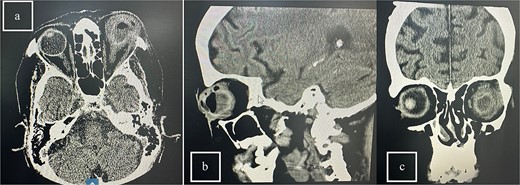

Patient 5: Fifteen days post-phacoemulsification, a 65-year-old Saudi female presented with no light perception (NPL) and severe lid edema (Fig. 9). B-scan revealed vitritis (Fig. 9). Figure 10 showing the B-Scan Ultrasound, illustrates the findings in Patient 5. Computed tomography (CT) scans of the orbit showed pan ophthalmitis (Fig. 11). She received intravitreal antibiotics immediately, followed by a pars plana vitrectomy.

Slit lamp examination of patient 5 showing (a) corneal haziness, (b) severe chemosis and ciliary injection, and (c) severe redness and swelling of the left upper lid.

CT scans of the orbit for patient 5 showing (a) coronal view with dense fluid content and air-fluid leveling, (b) axial view with edematous changes in the intra-conal fat, and (c) sagittal view with involvement of the extra-ocular muscles.